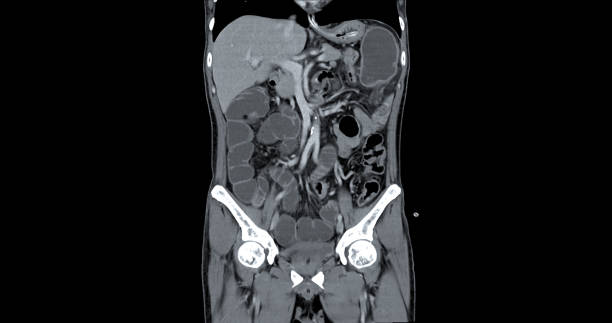

게실염은 대장 내부에 상황을 정확하게 파악하기 위해 대장내시경 검사가 필요할 수 있습니다.

따라서 게실염의 증상이 나타날 경우, 적절한 시기에 병원을 방문하여 의사의 진료와 검사를 받는 것이 중요합니다.

게실 염증을 방치할 경우 합병증으로 이어질 수 있으므로 조기 진단과 치료가 필요합니다.